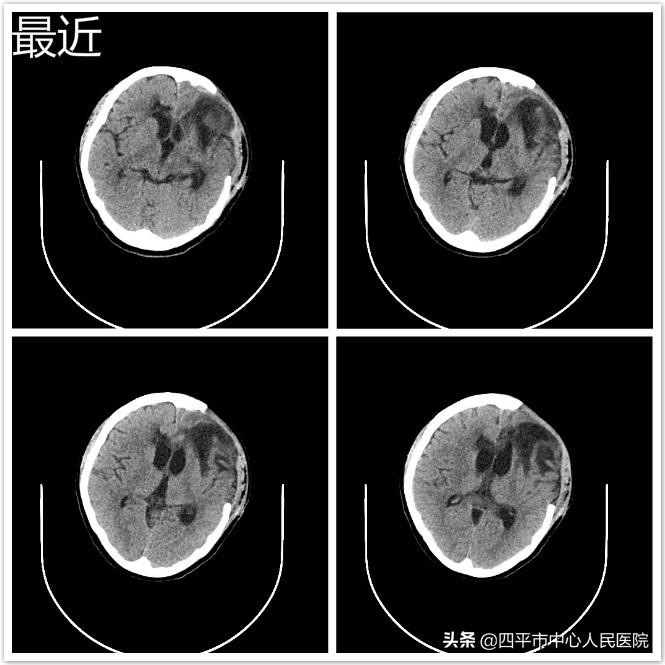

近日复查头部CT:左侧额颞部部分颅骨缺如,脑出血吸收良好,脑室系统正常大小。患者丈夫为神经外科送来锦旗表示感谢,激动地说:“李主任,是您给了我爱人第二次生命,我们家里多次商量后都想放弃治疗了,是您给了我们的希望,不仅拯救了孩子的妈妈,还拯救了我们整个家庭。”现在,患者已经转到血液科进一步治疗。

这例白血病继发脑出血严重凝血功能障碍病危患者经过我院多学科合作救治,不但恢复了意识,神清语明,而且四肢活动自如,没遗留任何后遗症。充分体现了我院作为四平及周边地区最大的三级甲等综合性医院的多科合作综合救治能力。